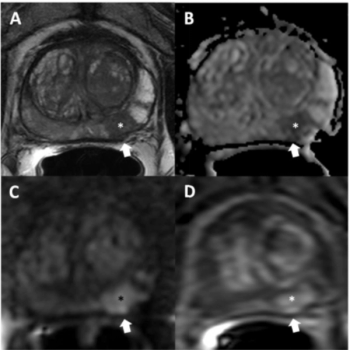

In the third part of a three-part interview from the recent RSNA conference, Mark Traill, M.D., discusses the potential of image-based risk assessment artificial intelligence (AI) algorithms in bolstering adherence to screening protocols for women at high risk for breast cancer.